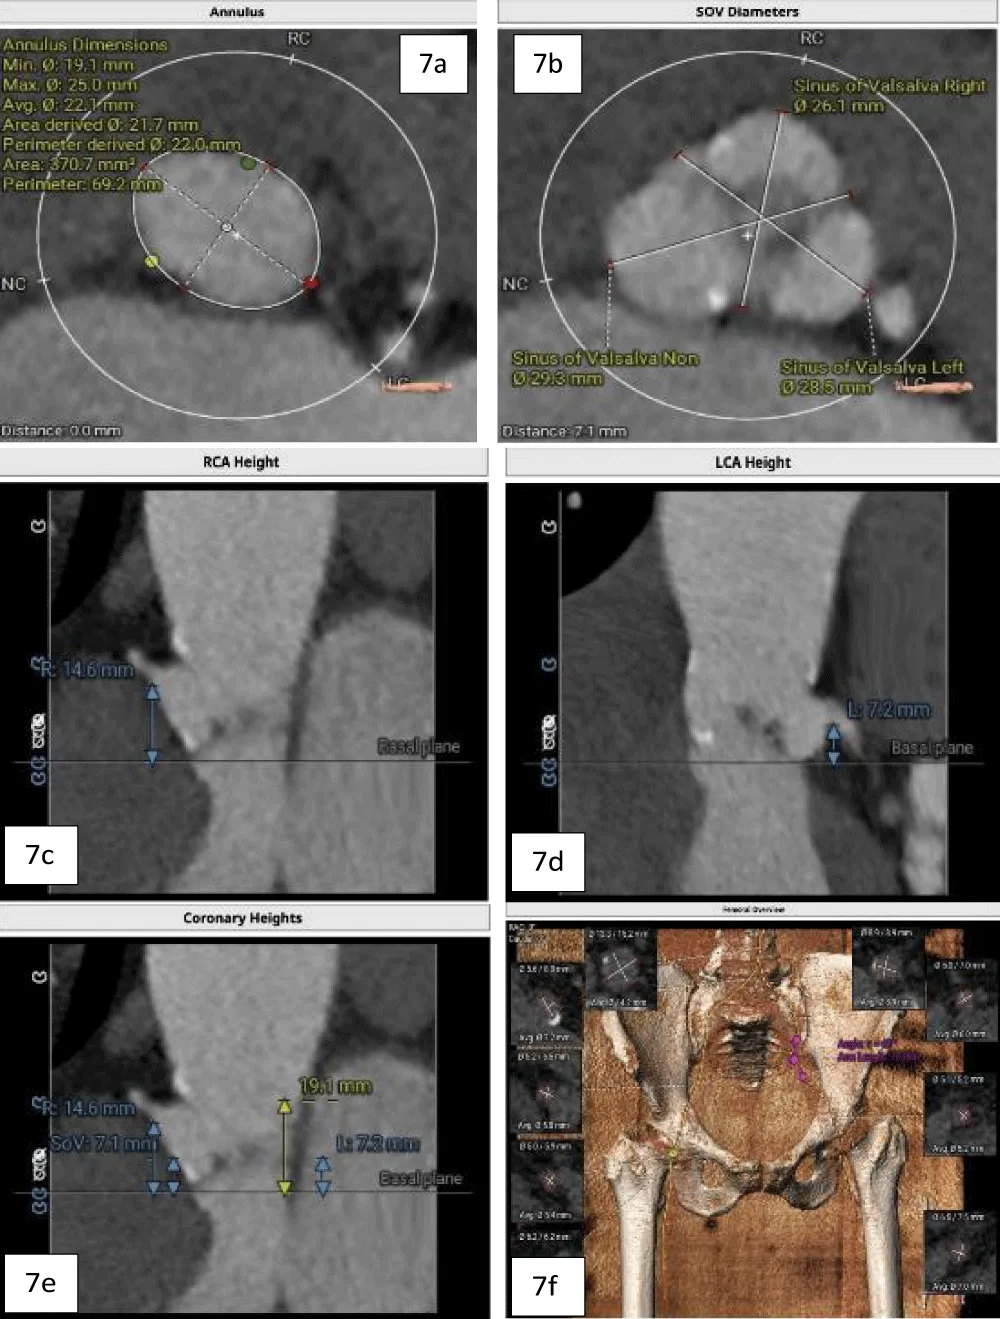

A 63-year-old female with morbid obesity (weight: 115 kg) presented with recurrent episodes of heart failure. On examination, an aortic systolic ejection murmur was audible, while the echocardiogram showed findings of severe AS with a mean gradient of 40 mmHg (Figure 6). Further, her coronary angiogram revealed non-obstructive CAD lesions in the right coronary and LAD arteries. The heart failure episodes were attributed due to severe AS; therefore, valve replacement was planned. The decision of the Heart Team was in favor of TAVI in view of the patient’s advanced age and morbid obesity. Hence, the anatomical eligibility for TAVI was assessed by contrast-enabled 3D computed tomography (CT) of the aortic root and the AV. The CT analysis revealed the bicuspid type 1a AV in the patient with fused right and left cusps. The average aortic annulus diameter was 22.1 mm, the annular area was 370.7 mm2, and the annulus perimeter was 69.2 mm (Figure 7a). The SOV diameters of the left, right, and non-coronary cusps are 28.5 mm, 26.1 mm, and 29.3 mm, respectively (Figure 7b). The heights of the RCO and LCO were 14.6 mm and 7.2 mm (Figure 7c,7d), respectively. The height of the SOV was 7.1 mm while the mean STJ height was 26.7 mm (Figure 7e). According to the iliofemoral analysis, the average diameter of the right common femoral artery (CFA) was 5.4 mm and that of the left CFA was 5.2 mm; the average diameter of the right external iliac artery (EIA) was 5.8 mm and that of the left EIA was 6.0 mm (Figure 7f).

Figure 7: a. Contrast-enhanced 2D-CT image showing the dimensions of the aortic valve annulus (mean annulus diameter: 22.1 mm and annulus perimeter: 69.2 mm), and b. showing the SOV diameters of the left, right, and non-coronary cusps. c. Height of the LCA (7.2 mm) shown with blue arrows, and d. Height of RCA (14.6 mm) shown with arrows. e. Height of the SOV 7.1 mm, shown with yellow arrows, and f. The diameters of the iliofemoral vessels at the access site.